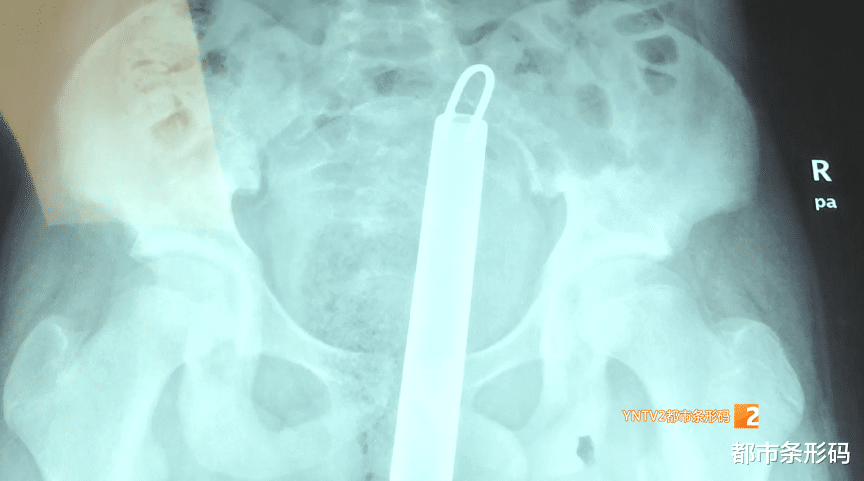

11月21日 , 12岁男孩浩浩不慎从宿舍上铺跌落 , 右臀部刚好落在拖把杆上 , 巨大的冲击力让拖把杆瞬间刺入他的盆腔近20公分 。

【南瓜|太危险!不慎跌落,拖把杆刺入12岁男孩盆腔!医院紧急救治】昆明医科大学第一附属医院儿科副主任医师 张洪斌:“钢管穿过直肠 , 到达骶骨 , 这个位置应该是骶1骶2的位置 。 ”

昆明医科大学第一附属医院儿科副主任医师 张洪斌:“小朋友因为肥胖 , 12岁有75公斤 , 打开腹腔整个肠道肠内物比较多 , 第二腹腔里的大网膜非常肥厚(空间狭窄) , 所以暴露手术视野非常困难, 另外钢管的位置在盆腔底部 , 我们打开是看不到的 , 只有通过打开骶前间隙才能找到钢管 。 ”

如果直接拔除拖把杆 , 可能会导致骶前血管大出血 , 还有可能导致严重感染 。 手术团队决定远端离断肠管 , 对远端直肠和骶前间隙进行充分冲洗后再拔除拖把杆 。